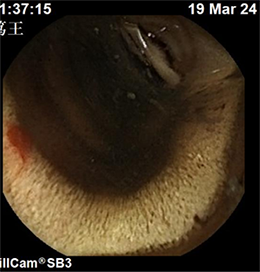

下图可见小肠内新鲜活动性出血